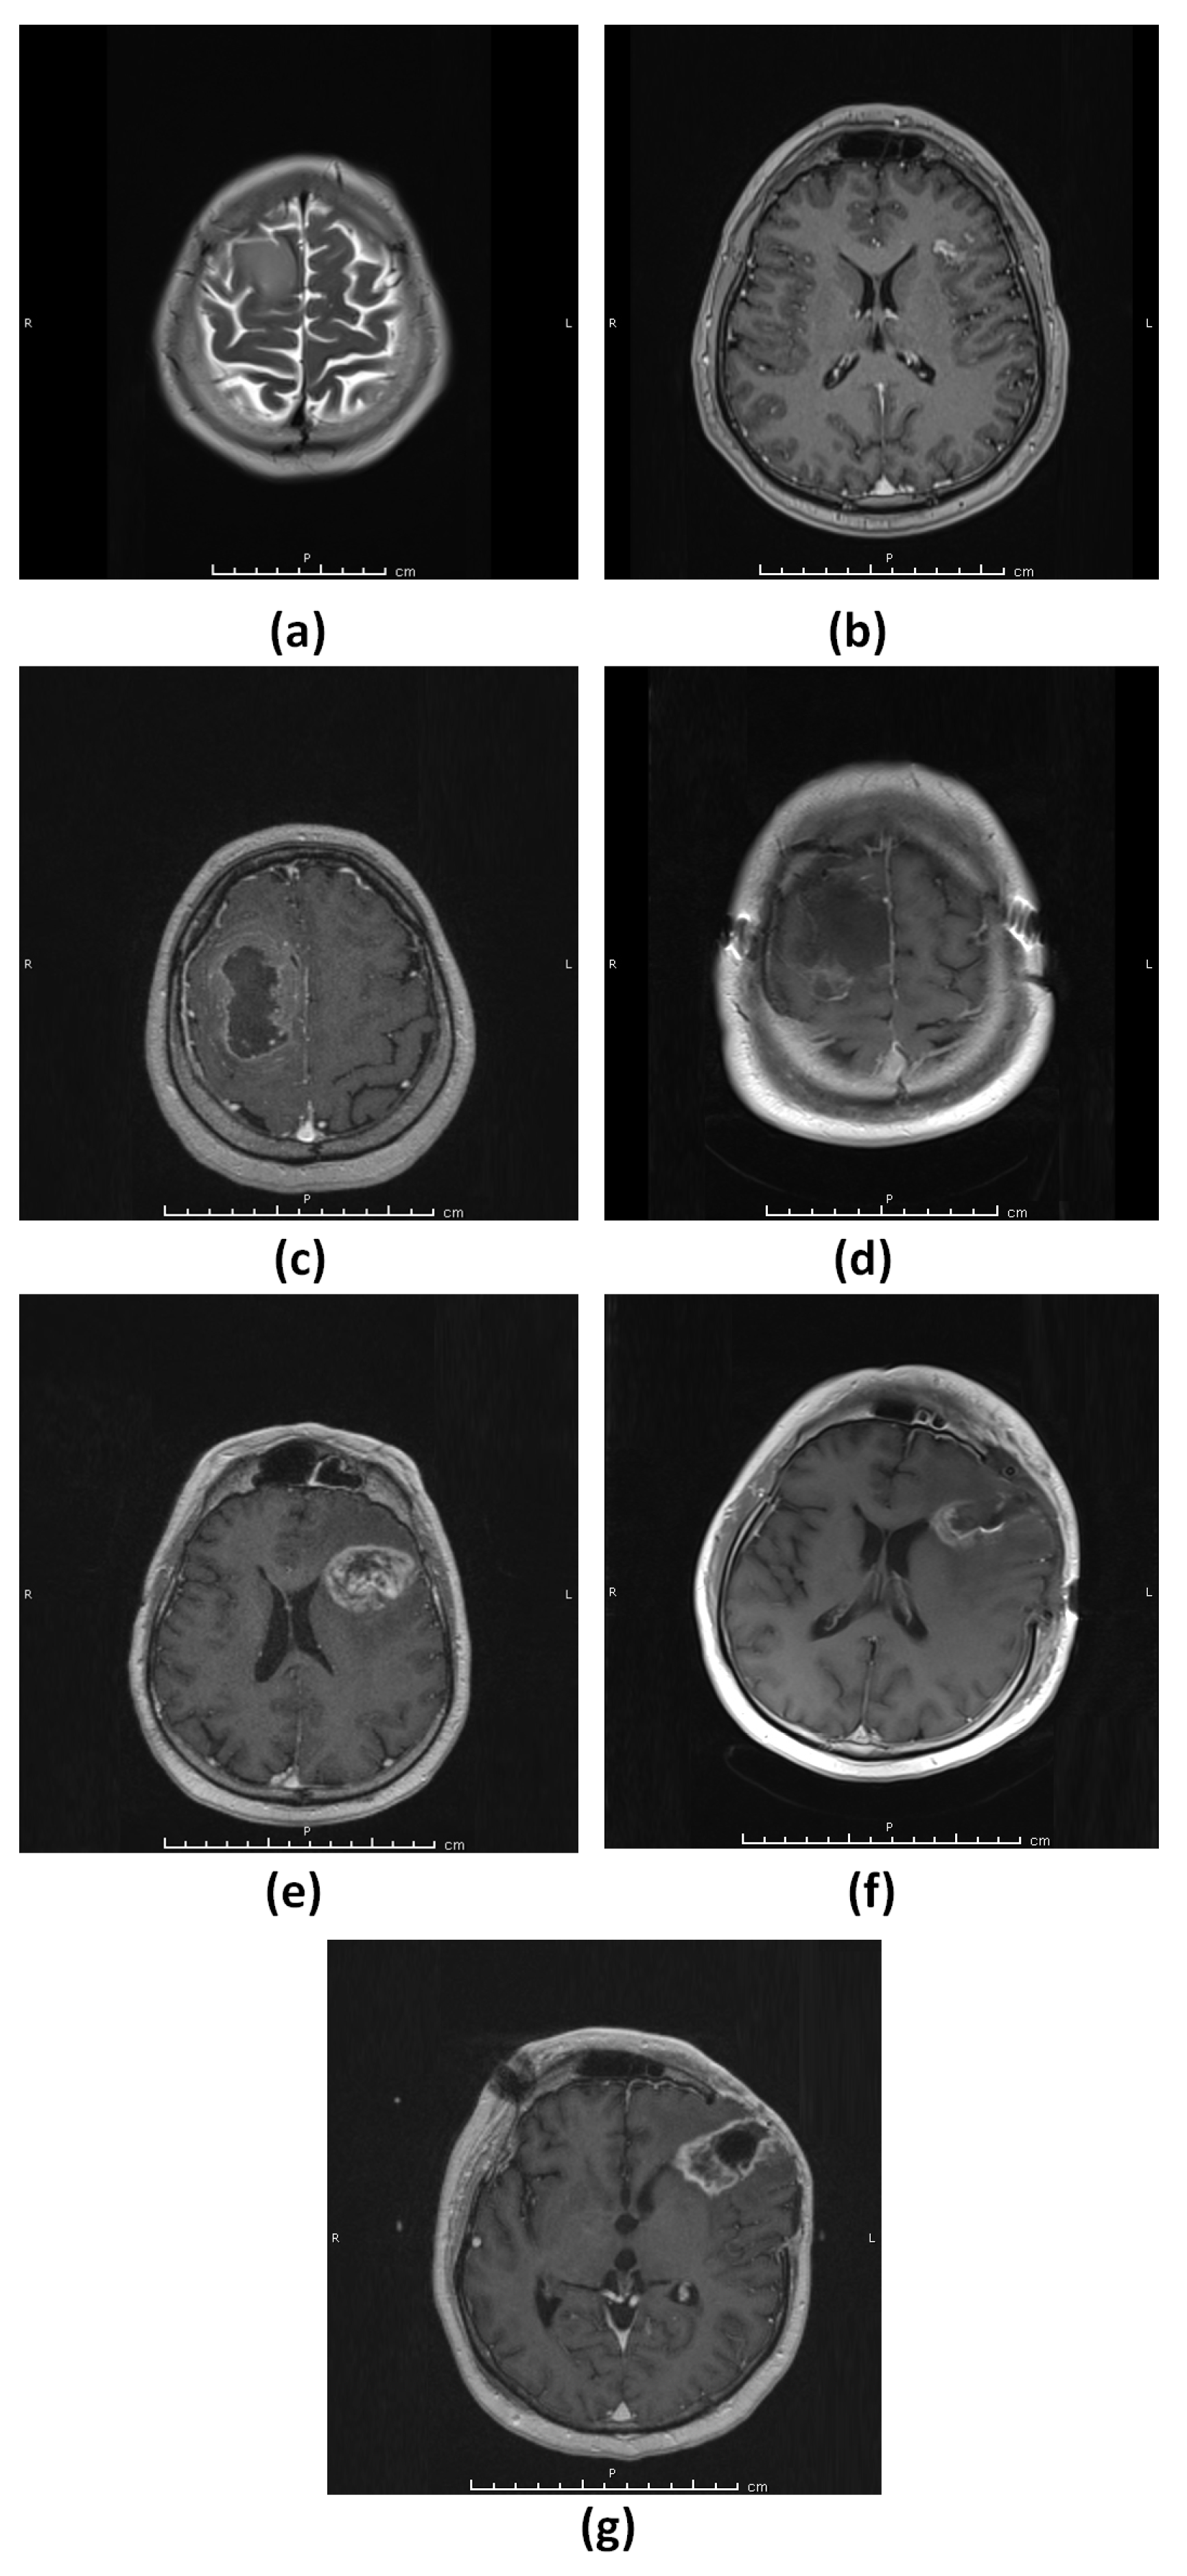

3.1.1. Patient 1 (G1)

3.1.2. Patient 2 (G2)

3.1.3. Patient 3 (G3–4)

3.1.4. Patient 4 (G5)